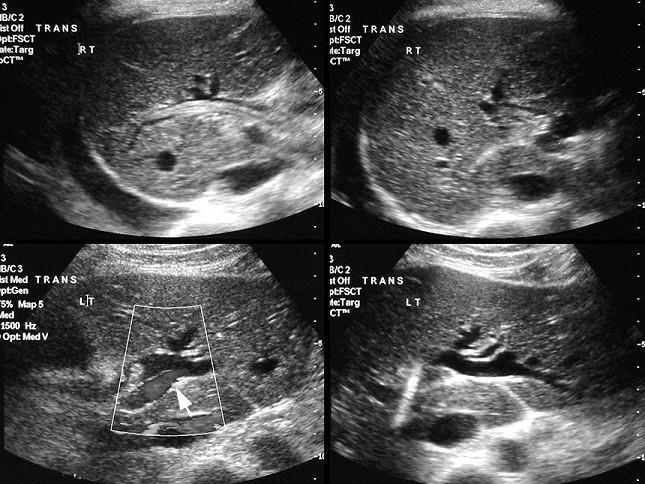

选项 A、阑尾炎的压痛、反跳痛主要在右下腹 B、胆道蛔虫病常出现腹膜刺激征 C、胃、十二指肠溃疡穿孔的压痛、反跳痛以上腹部最明显 D、胰腺炎病人血尿淀粉酶增高 E、胆总管结石的腹痛常伴发热和黄疸